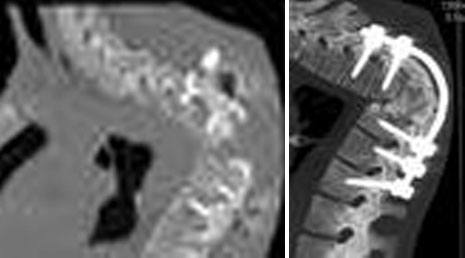

42. OPLL- corpectomy

43. OPLL- laminoplasty